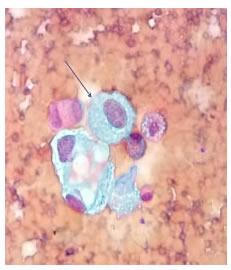

Figura 3.

Citología de líquido pericárdico. Se observa un fondo

hemorrágico, células mesoteliales con cambios reactivos y discreto

aumento del núcleo y el citoplasma (flecha). Diagnóstico: mesotelio

reactivo. Tinción de Papanicolaou, 40X.

Se realizó una ventana pericárdica más pericardiectomía e instalación de un catéter pleuro-pericárdico subcutáneo (tunnelized) mediante toracoscopia izquierda. El líquido pericárdico era de color cetrino. No se identificó carcinomatosis pleural o pericárdica. El examen citológico del líquido pericárdico fue negativo para neoplasia maligna y en la histopatología de las biopsias de pericardio y de pleura parietal se observó un mesotelio reactivo, negativo paraneoplasia maligna (figura 3).